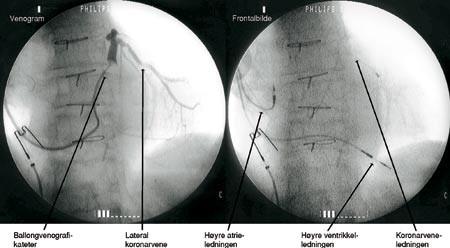

Metoden er tidligere beskrevet i Tidsskriftet (2). Via v. subclavia plasseres en innføringshylse i stabil posisjon i sinus coronarius, og gjennom denne et venografikateter med en lateksballong på tuppen (fig 2). Denne ballongen blåses opp til en diameter på 10 mm og okkluderer sinus coronarius helt eller delvis mens man injiserer kontrastvæske og tar røntgenbilde og film av koronarvenene. Man benytter også samme type tynne ledesonder med diameter 0,356 – 0,475 mm som ved perkutan koronar intervensjon av koronararteriestenoser for å manøvrere seg inn i de tynne koronarvenene. Pacemakerledningen føres så over denne tynne ledesonden. Man tilstreber å få spissen plassert i en lateral koronarvene. Deretter innføres pacemakerledninger til høyre ventrikkel og til høyre atrium (fig 1).